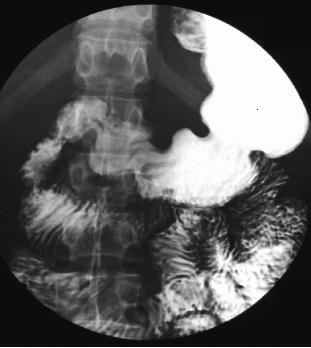

. La TOGD en double de contrast ( baryt + air +

hypotonie medicamentuese ) peut evite la superposition du

duodenum et du grele sur estomac et ce qui augemente

detection detaillee de la muqueuse gastrique et les niches de face de

l'estoma . Cette methode essentiellement utilisee pour estoma et le

colon , et rarement sur l'intestin grele .

| TOGD de estomac normale en

double de contrast |

Ulcere de la petite courbure en double de

contrast |

Images en double de contrast

d'une ulcere du paroi posterieure de estomac . |